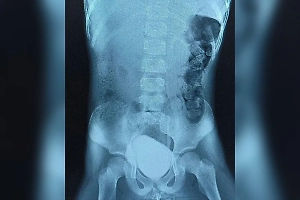

В Приморье медики совершили настоящее чудо, восстановив лицо девушки после серьёзного ДТП. 20-летняя пациентка получила тяжелейшие увечья: металлическая труба забора прошла прямо сквозь её шею и частично разрушила лицо. Врачам пришлось буквально собирать девушке осколки костей и восстанавливать утраченную анатомию. Об этом сообщает пресс-служба Минздрава Приморья.

«Мы аккуратно собрали нижнюю челюсть, провели остеосинтез титановыми пластинами и зафиксировали подъязычную кость в правильном анатомическом положении. Также выполнили вторичную хирургическую обработку ран с замещением имеющихся дефектов, что было очень непросто - работать пришлось в условиях выраженного воспаления», — рассказал заведующий отделением челюстно-лицевой хирургии Алексей Романчук.

Медики использовали специальные титановые конструкции, что позволило восстановить структуру черепа и лицевых тканей пациентки. Сейчас девушка вновь способна самостоятельно питаться и говорить, радуется жизни и выражает огромную благодарность медикам.